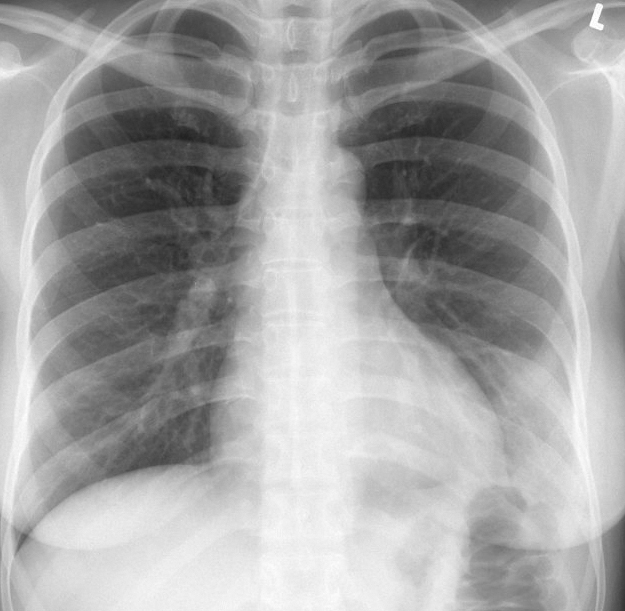

Gallery Pneumonia Case 12 antmed LLL pneum PA

Case 12 antmed LLL pneum PA